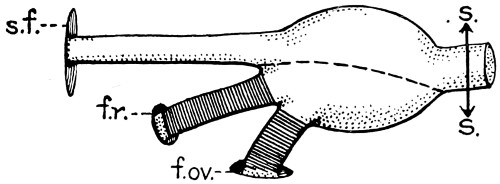

| 26. The author’s operation for Hydrocephalus internus | 64 |

| 27. The conversion of Hydrocephalus internus into cephalocele | 65 |

L. BATHE RAWLING.

April 1912.